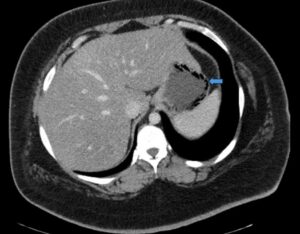

Gastric Emphysema. Axial CT, annotated. JETem 2024

Gastric Emphysema. Axial CT annotated. JETem 2024